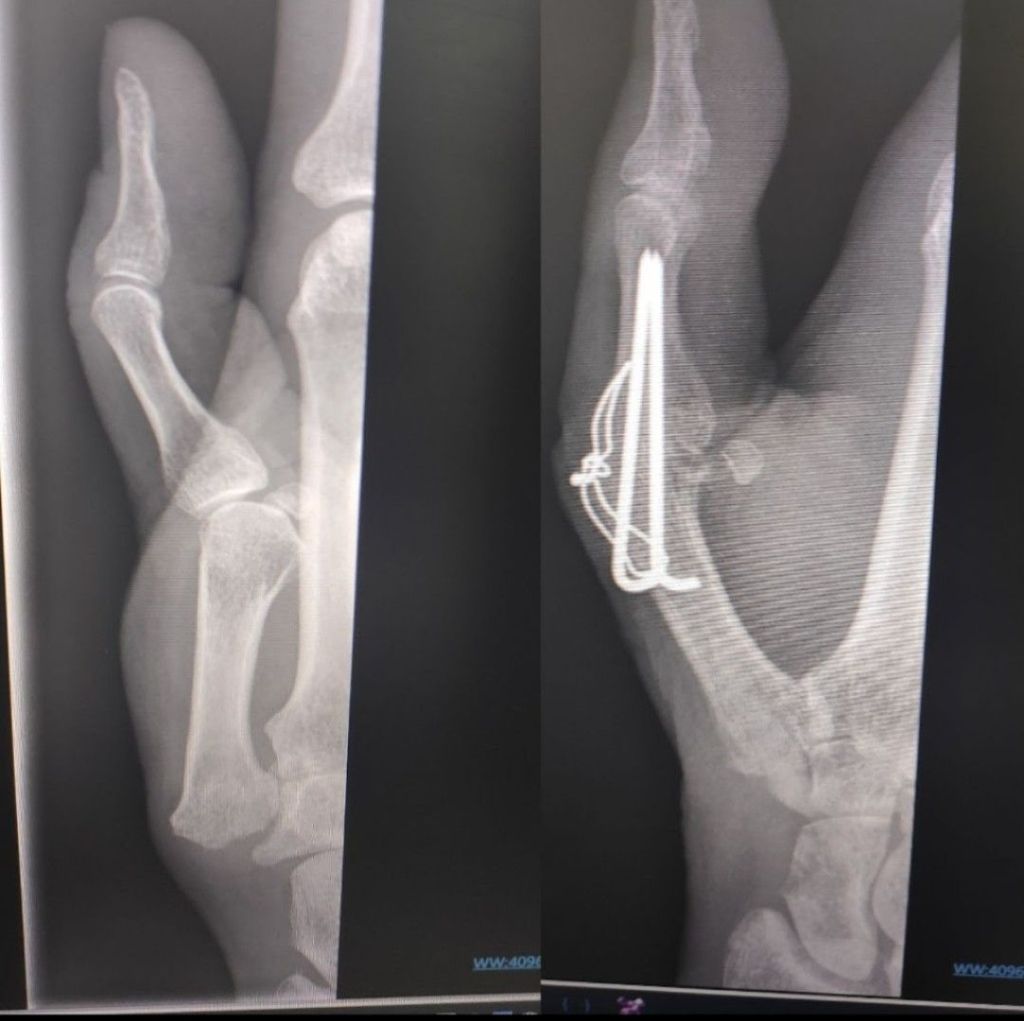

The knot in the wire is why I really wanted this appointment. It pokes through, hurts and scar tissue is building up.

We agreed the wire needs to come out, and actually it might be the reason I can’t flex my Dip joint (tip of thumb) because the tendon may be stuck due to the scar tissue, so they suggested an Extensor Tendolysis.